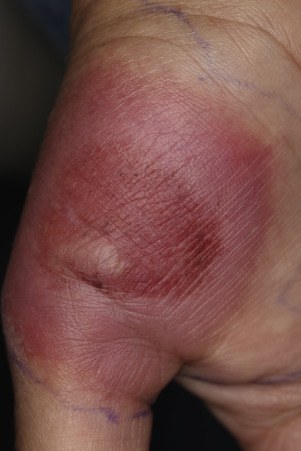

Most spider bites cause pain at the instant they occur. A hive-like swelling appears at the bite site and expands radially, usually for just a few centimeters ( Figs. 15.24 and 15.25

); however, the swelling can sometimes reach gigantic proportions. Occasionally, two puncta or fang marks can be found on the skin surface. The warmth and deep erythema of a bite may resemble bacterial cellulitis, but the hive-like swelling and small, satellite hives are not characteristic of bacterial infection. A biopsy, although usually not necessary for diagnosis, may show mouth parts and intense inflammation. The lesion resolves spontaneously, but itching and swelling can be controlled with cool compresses and antihistamines.